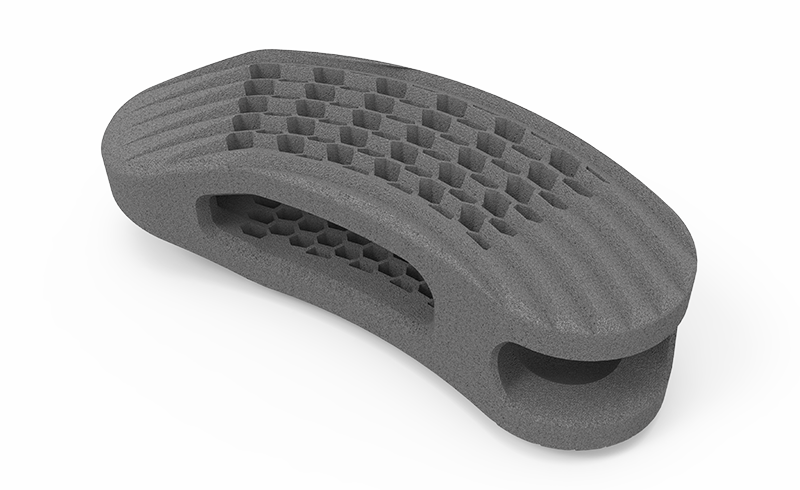

zurückDeltacorCages

Cages

Alle Modelle nun mit der patentierten hygroskopischen Struktur. Diese Kapillarwirkung beeinflusst das Einwachsverhalten positiv ohne Verwendung von autologem Knochen.

zurückLOCC-SLMPLIF aus Titan

LOCC bedeutet »Lateral Offset Contact Cage«. Der Name steht für eine optimal laterale Abstützung. Durch sein kurviertes Design am lateralen Anteil wird eine zusätzliche Abstützung am äußeren Rand des Wirbelkörpers generiert. Die Last wird somit auf den gesamten Wirbelkörper sicher verteilt.